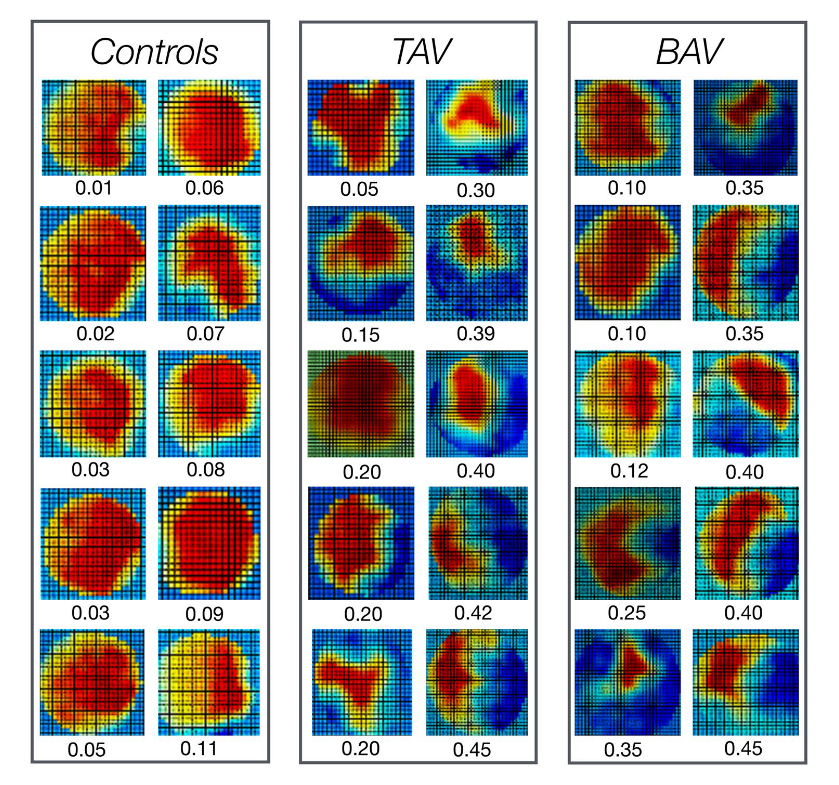

Flow displacement is used to describe the eccentricity of the outflow jet.